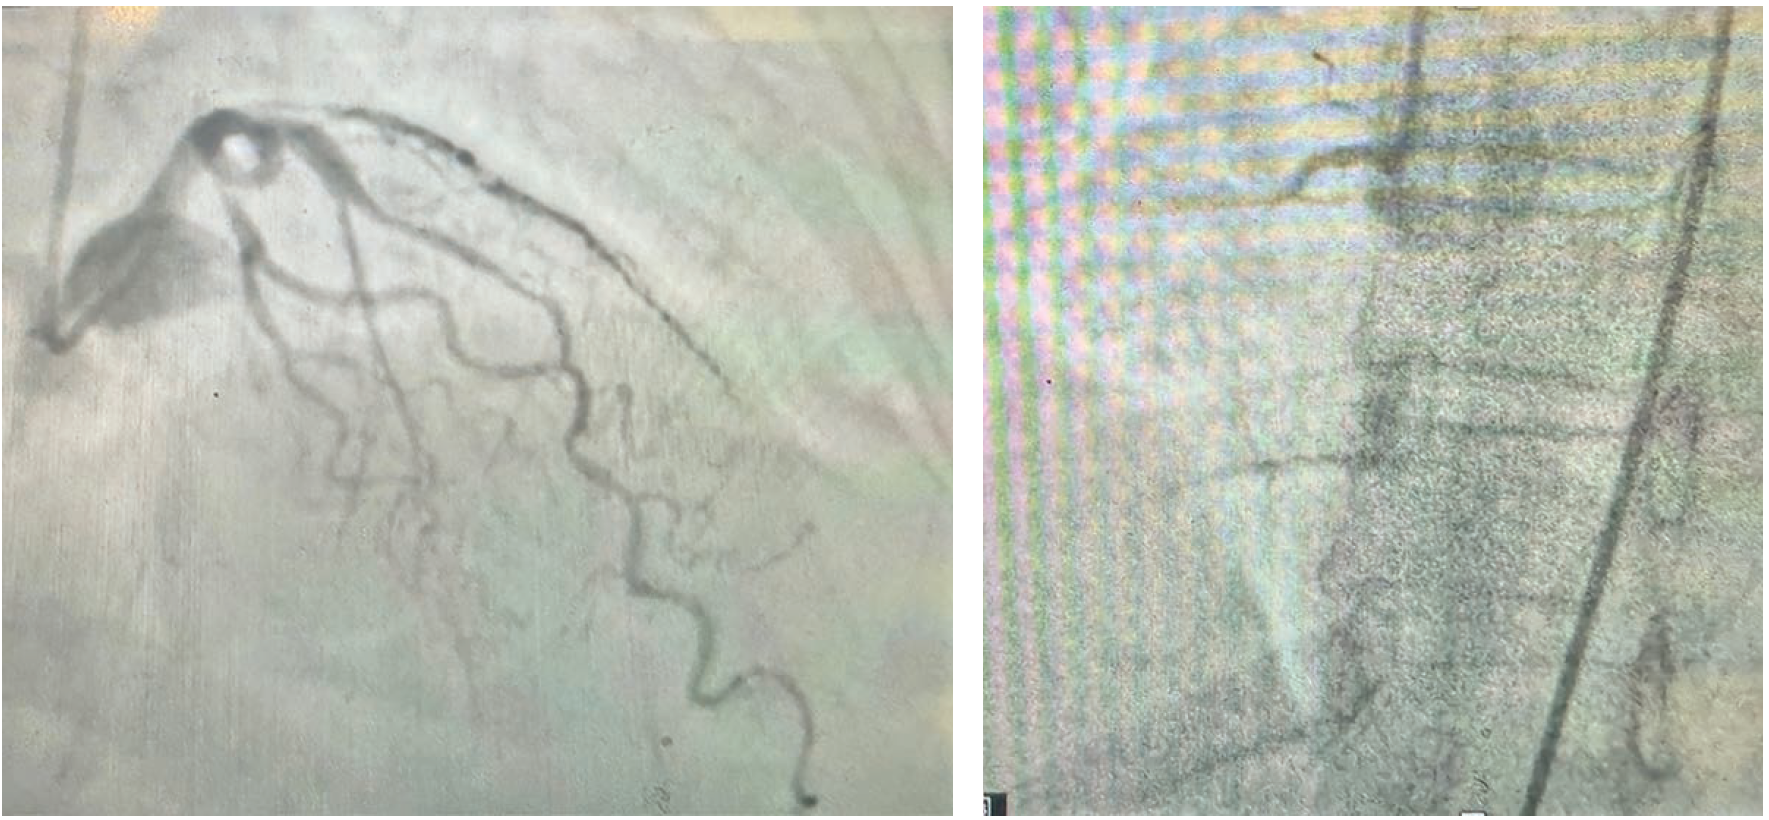

A 70-year-old female with no significant medical history presented with two hours of worsening left-sided chest discomfort and diaphoresis. An electrocardiogram (ECG) revealed acute inferior ST-elevation myocardial infarction (STEMI) (Figure 1). Coronary angiography showed a 60%-70% stenosis involving the proximal-mid left anterior descending (LAD) coronary artery with the appearance of spontaneous coronary artery dissection (SCAD) and a 100% occluded proximal right coronary artery (RCA) (Figure 2A-B).

After failing to cross the lesion with a workhorse wire, a Pilot 50 (Abbott) was successful. Percutaneous transluminal coronary angioplasty (PTCA) was unsuccessful in restoration of TIMI flow. Intravascular ultrasound (IVUS) showed a large intramural hematoma (IMH) in the distal RCA and severe stenosis with the presence of fibrofatty plaque through the proximal RCA (Video 1) (Figure 3). A Penumbra mechanical thrombectomy catheter was inserted and intracoronary (IC) injection revealed flow in the distal coronary bed. Mechanical thrombectomy was unsuccessful as well (Video 2), chosen in consideration of a thrombotic component contributing to this unusual STEMI. The Penumbra catheter was re-inserted, and IC 200 mcg of nicardipine was administered, which also failed. One mg of IC tPA was then injected, which restored flow (Video 3). Next, 2.75 mm x 38 mm and a 3.0 mm x 48 mm drug-eluting stents from the mid distal to the proximal RCA were successfully deployed (Video 4). Post percutaneous coronary intervention IVUS revealed well apposed and expanded stents (Video 5). The patient was discharged 2 days later on guideline-directed medical therapy. An outpatient workup for fibromuscular dysplasia was unremarkable.